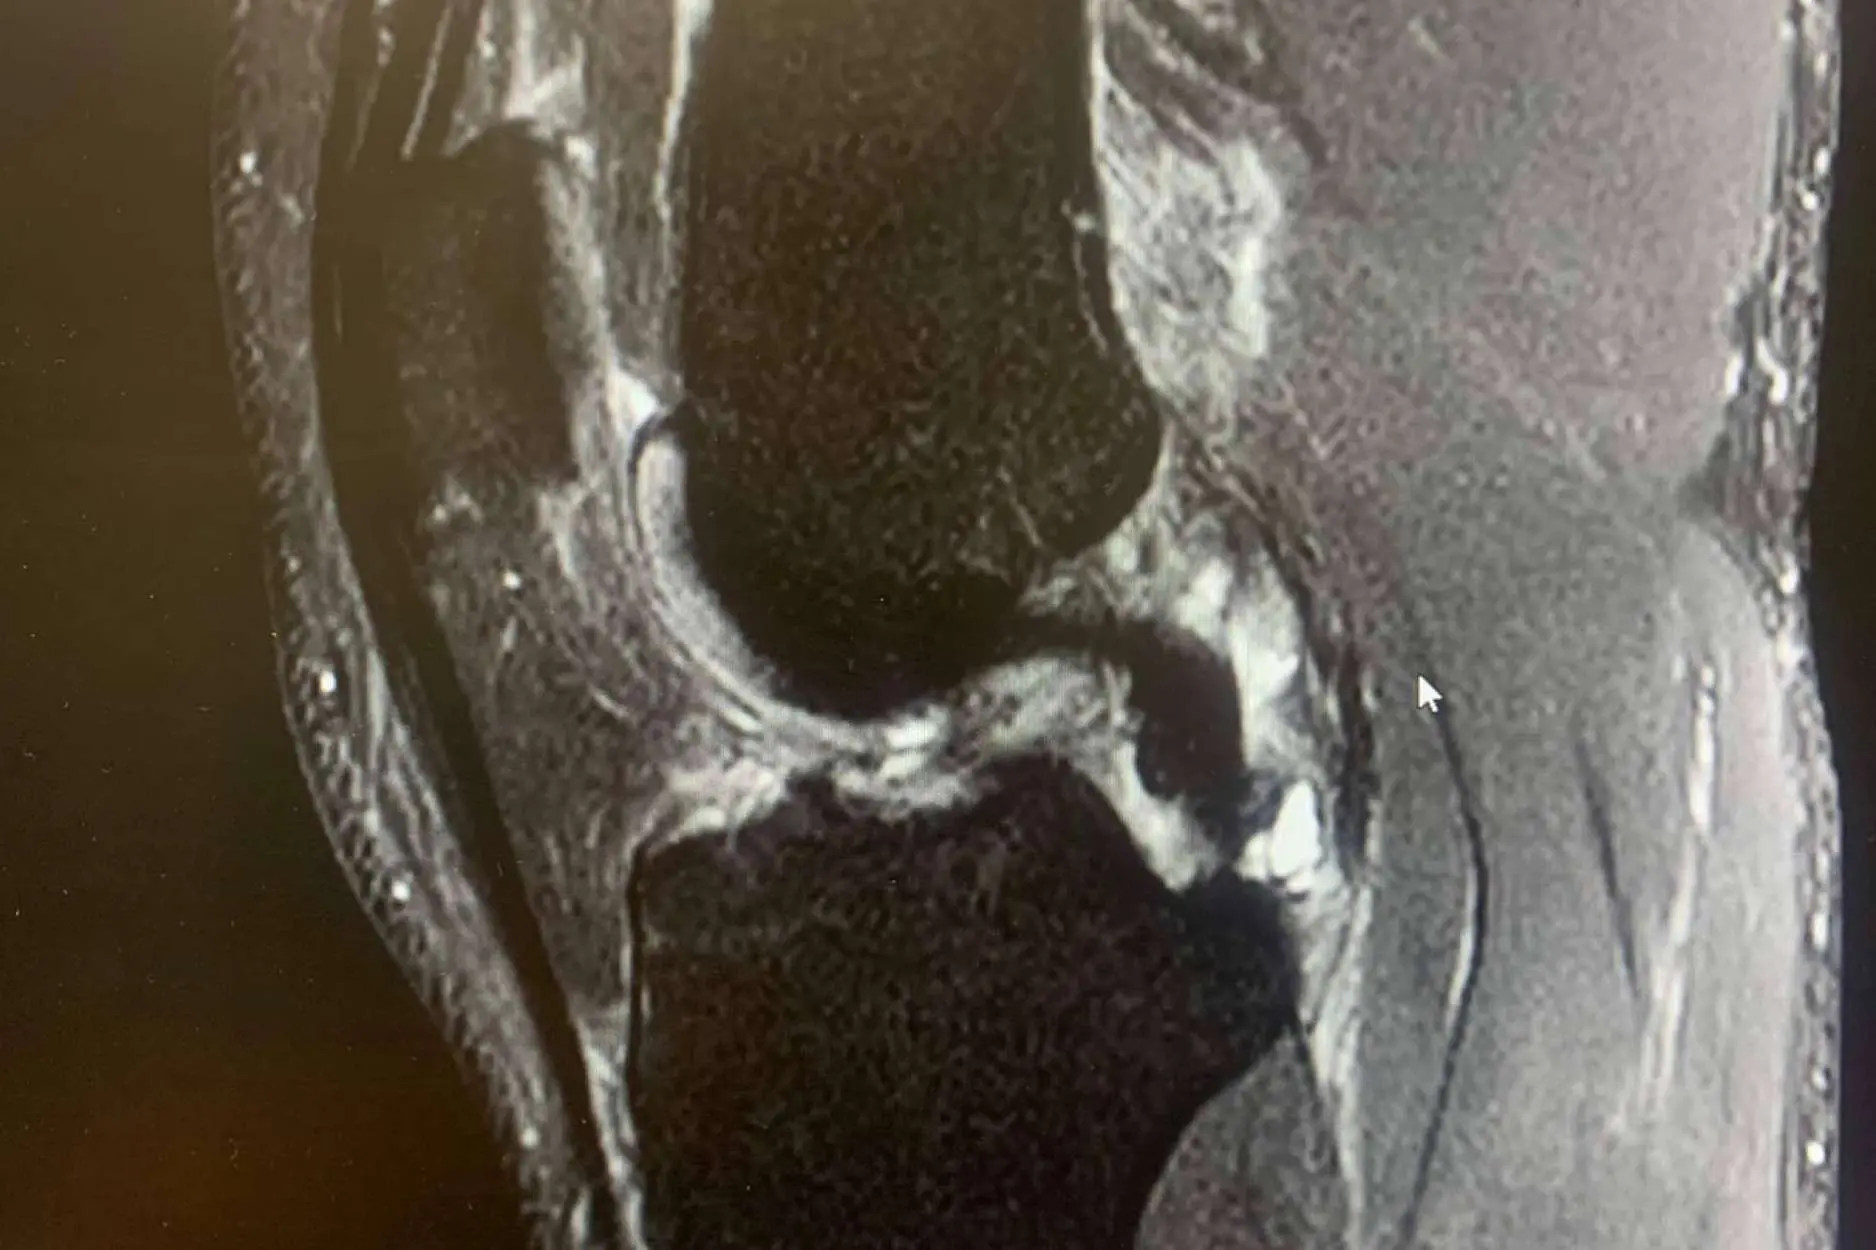

El ligamento cruzado anterior es una banda de tejido fuerte y resistente que se encuentra en la rodilla y juega un papel crucial tanto en la estabilidad como en la capacidad de control de esta articulación.

Las lesiones de LCA suelen ocurrir en situaciones en las que la rodilla está sometida a un estrés repentino y excesivo, sobre todo cuando la pierna está en apoyo y se somete a una torcedura en valgo (“metiendo la rodilla hacia dentro”) o con una torsión de la pierna hacia afuera con torsión interna del muslo, con la rodilla en flexión.

Una caída o un giro inesperado en la vida cotidiana puede causar una lesión en el LCA. Los síntomas de una lesión del ligamento cruzado anterior (LCA) pueden variar en intensidad según la gravedad de la lesión.

Derrame articular: Si el traumatólogo lo tiene que extraer mediante punción para aliviar la presión y el líquido es rojo (“hemático”), es probable que se trate de una lesión del LCA, aunque puede tener otras causas.